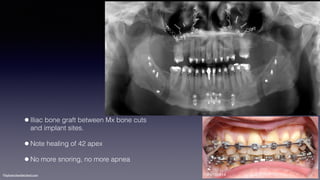

•Iliac bone graft between Mx bone cuts

and implant sites.

•Note healing of 42 apex

•No more snoring, no more apnea